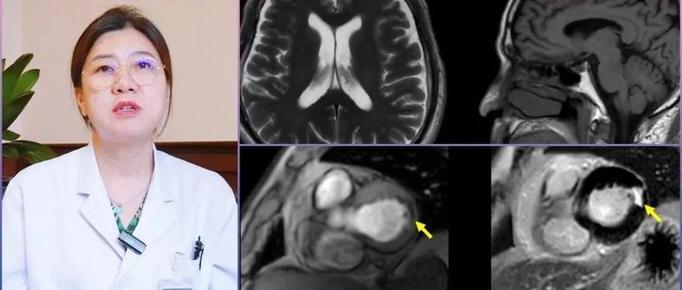

三者之间的“恶性循环”

这三种疾病通过共同的病理基础和直接的因果关系,紧密地联系在一起。

(图片来源网络,侵删)